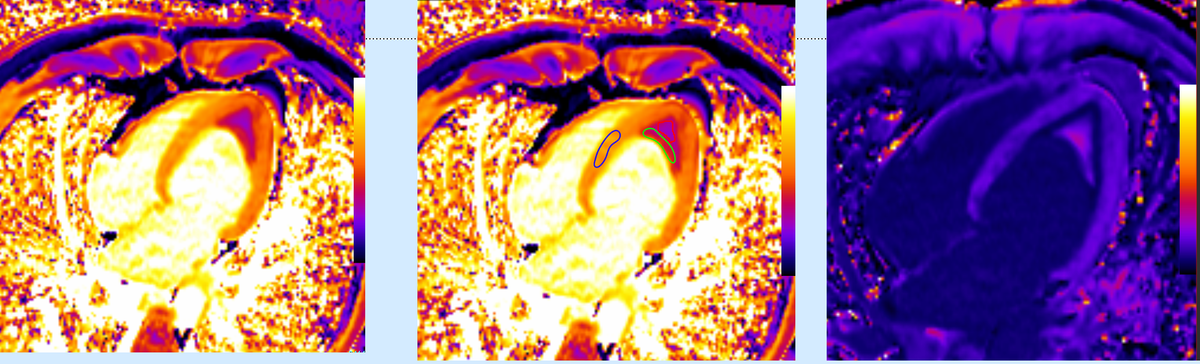

The Value of Extracellular Volume (ECV) in ATTR - Transthyretin Amyloidosis

Cardiac MRI is a useful tool to diagnose amyloidosis. T1 mapping has become a mainstay, both native and ECV measurements. ECV measurement can now help quantify the amyloidosis burden and may help guide treatment based on how the ECV responds to specific treatment measures.